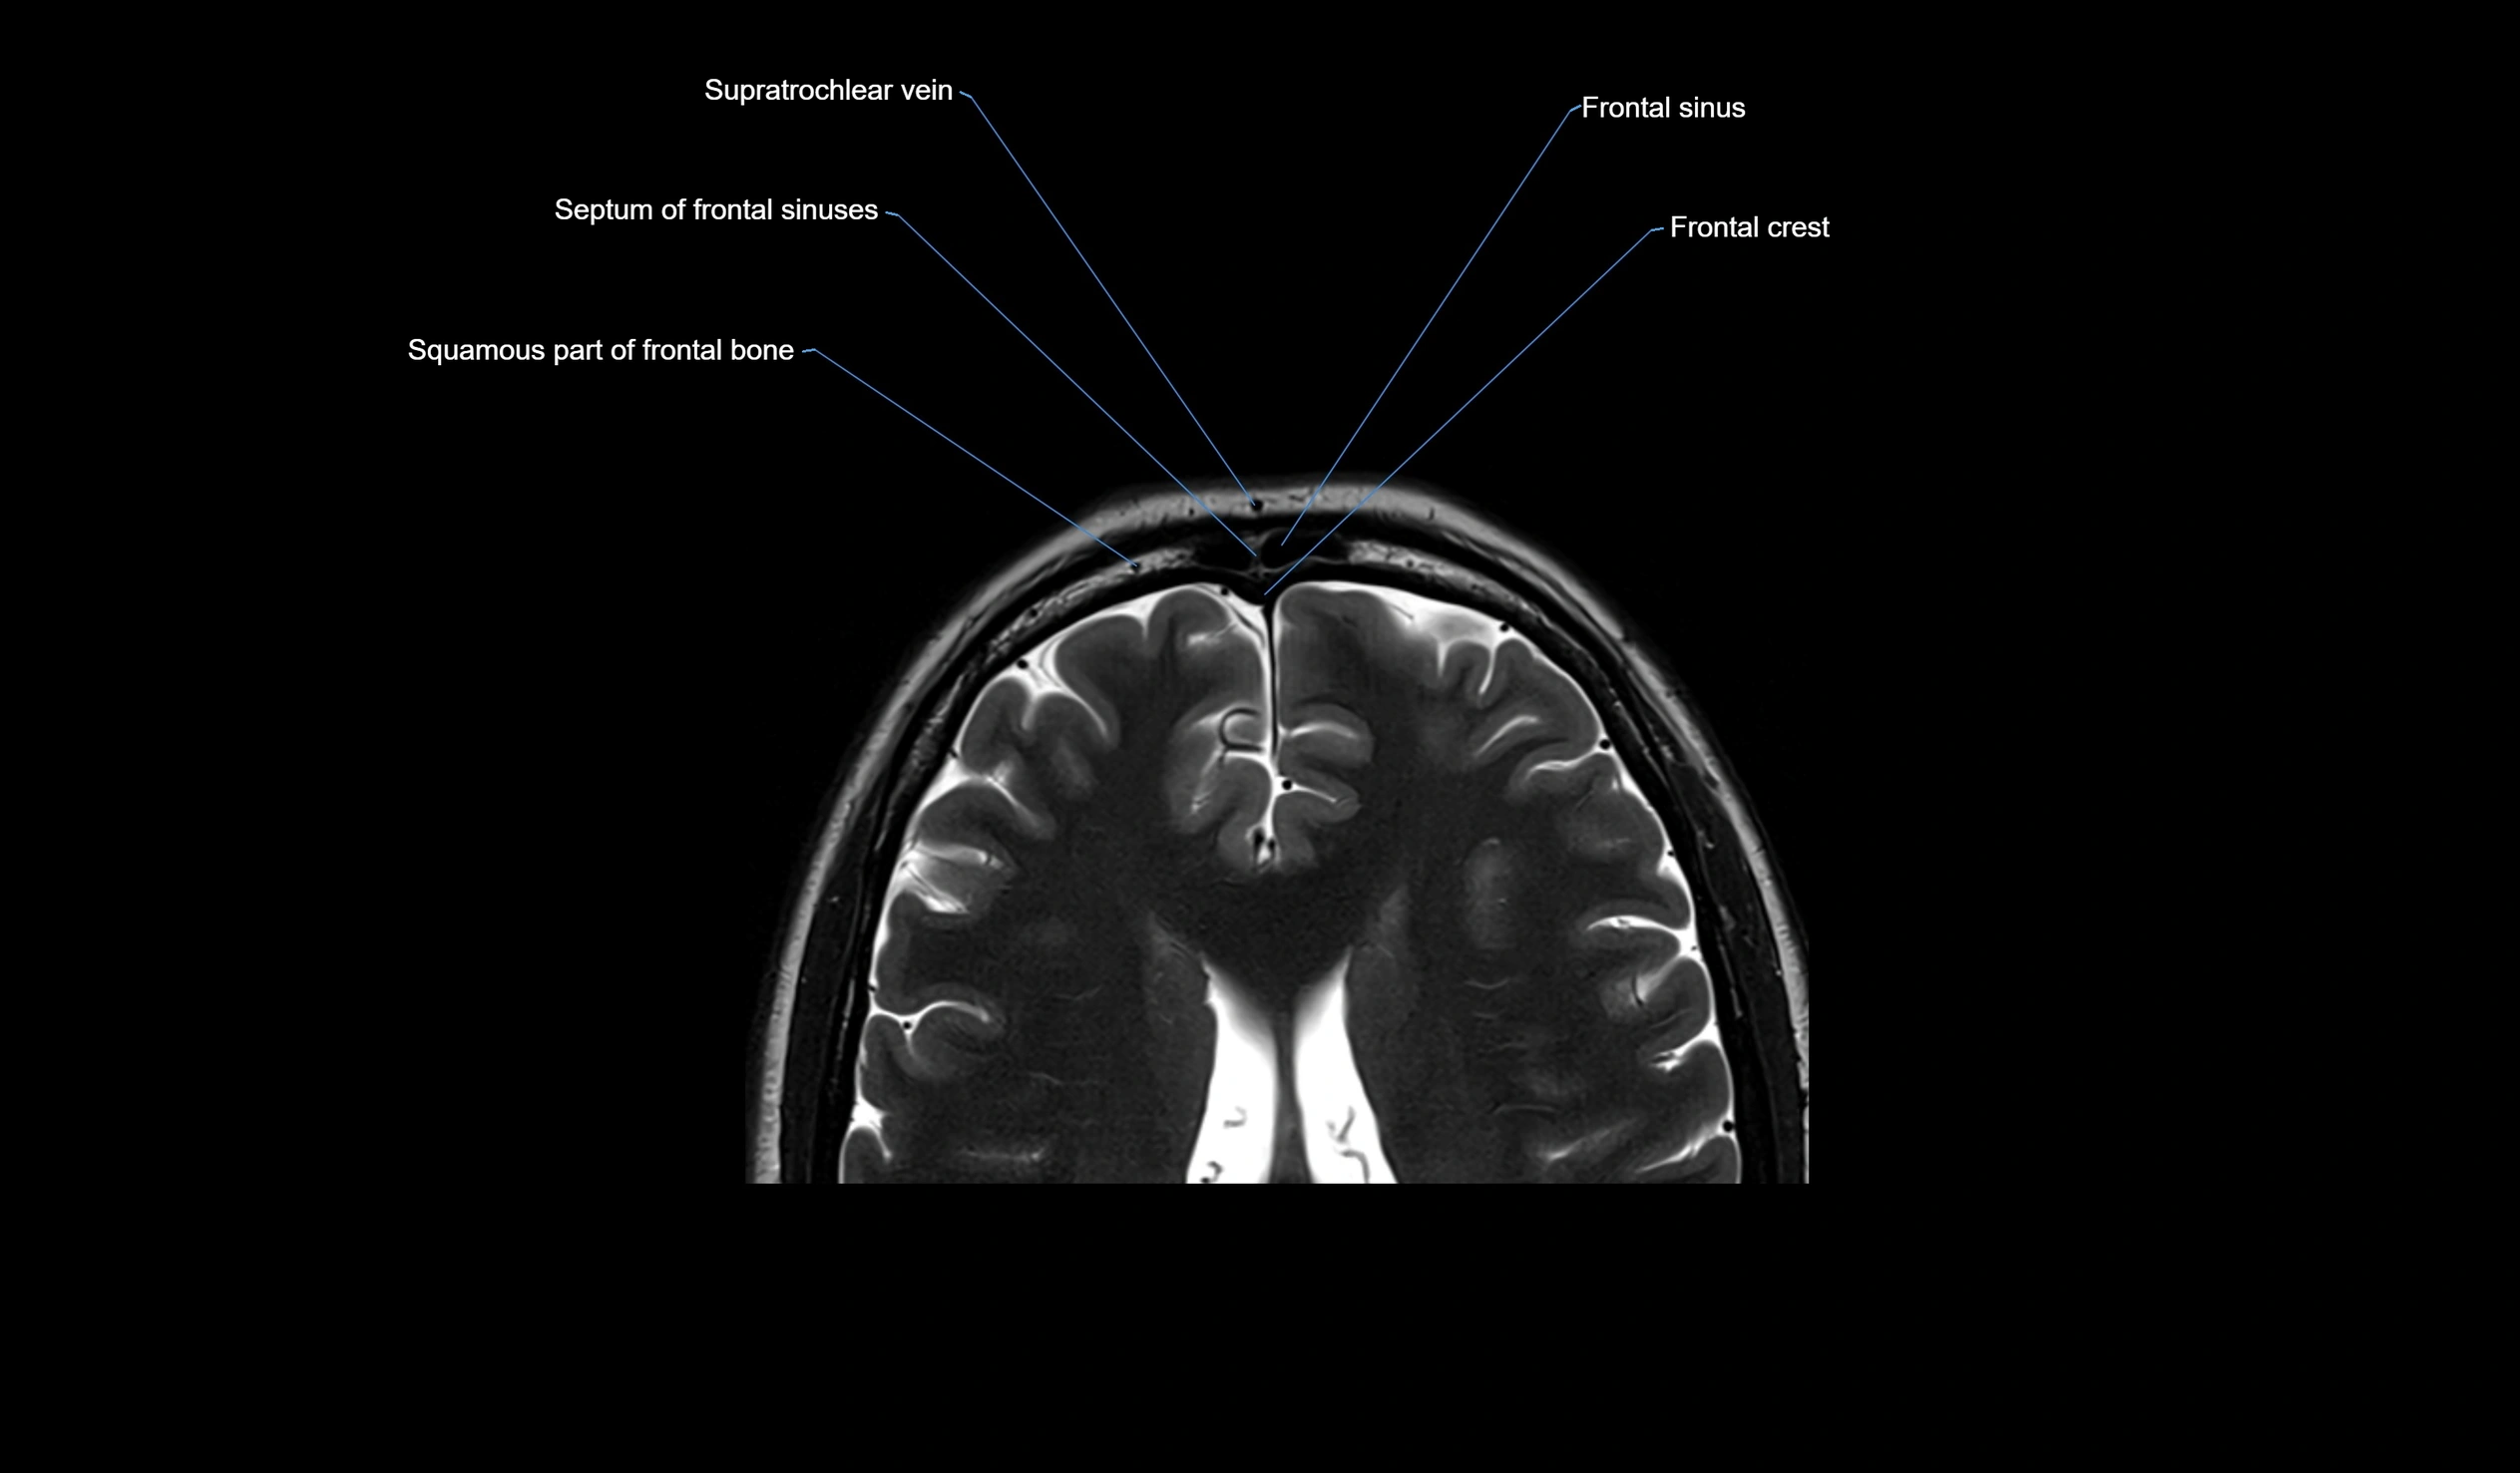

- Frontal sinus

- Supratrochlear vein